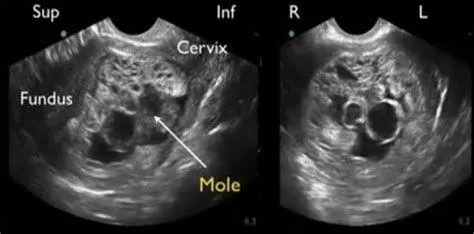

"Deteksi dini melalui pemeriksaan ultrasonografi (USG) adalah kunci utama. Gambaran 'snowstorm' atau badai salju pada layar USG merupakan tanda khas yang menunjukkan adanya jaringan kista di dalam rahim." - Pakar Ginekologi